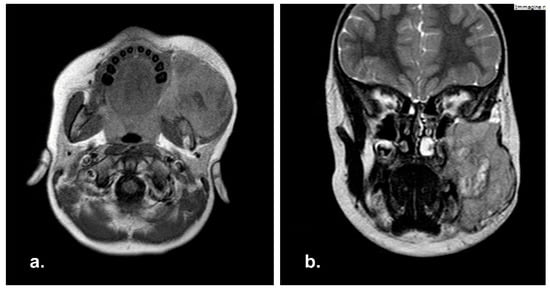

MRI scan was performed, showing an extensive infiltrative mass of 4 × 2.9 × 3.6 cm extending into right maxillary sinus. No cervical lymphadenopathy was reported (Figure 1).

Figure 1. Pre-operative Magnetic Resonance Imaging (MRI) in coronal (a) and axial (b) view showing a well-demarcated mass in right maxillary sinus with extension in the right hard palate.